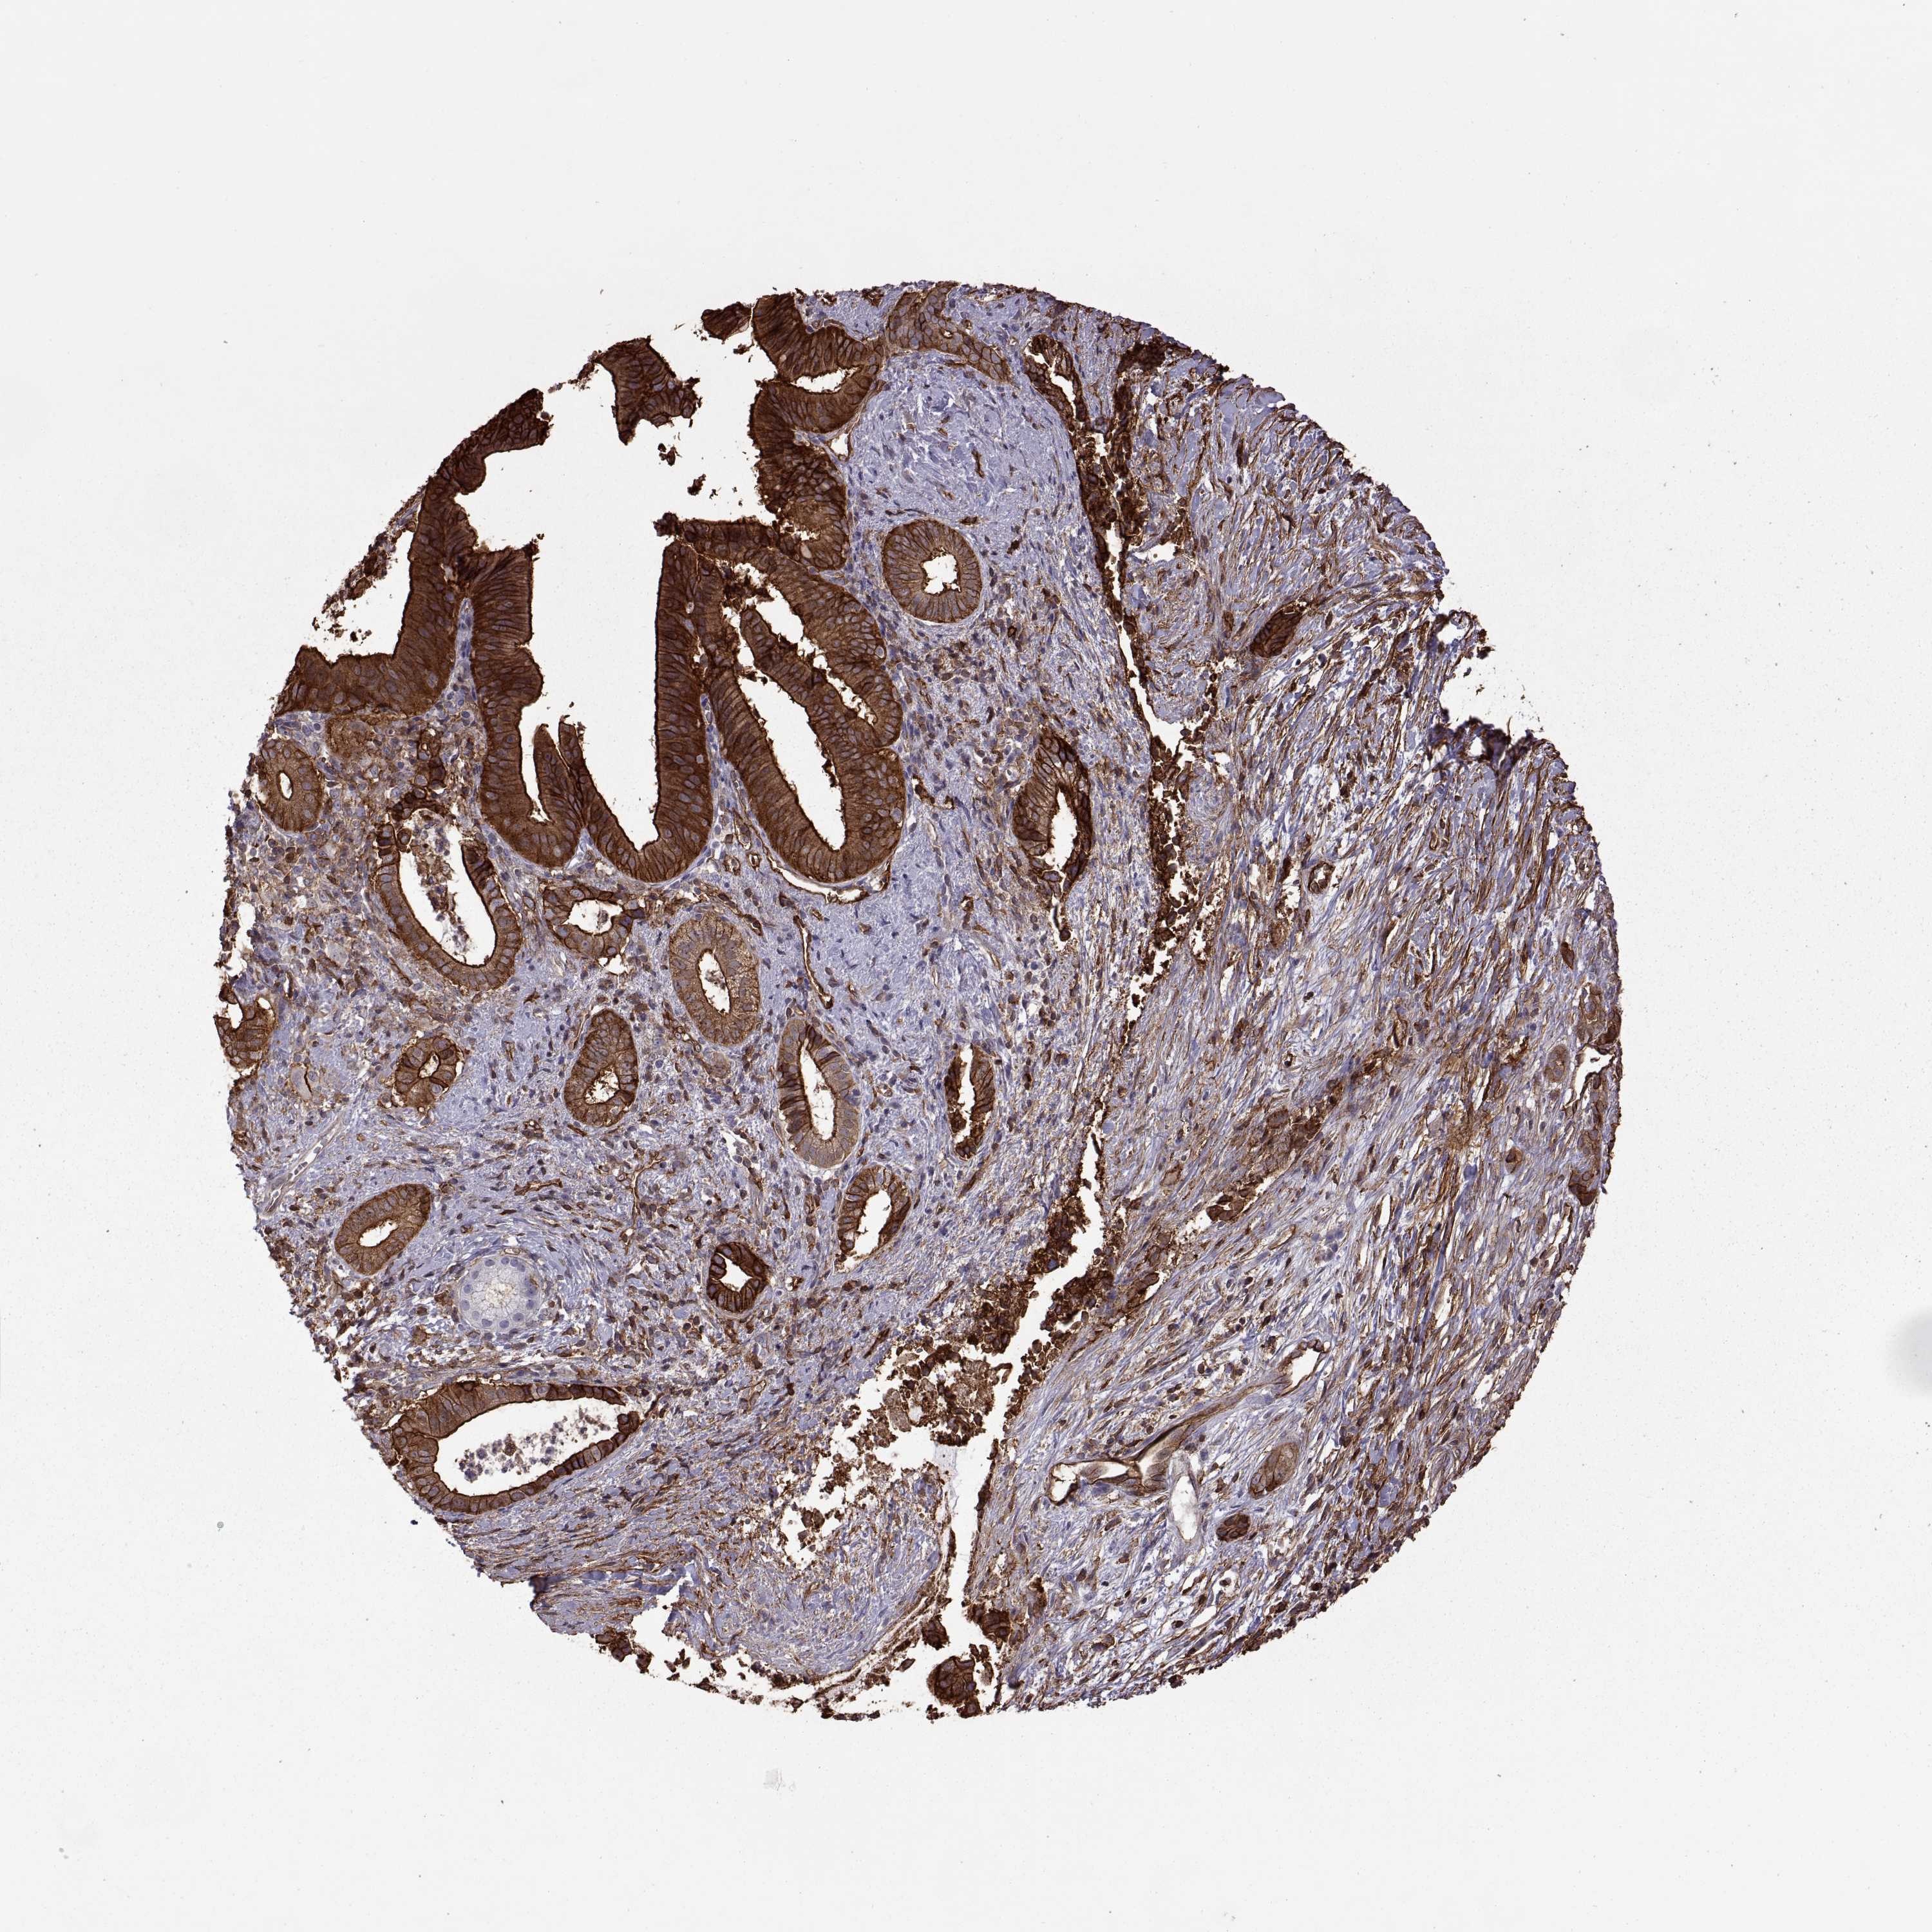

PANCREATIC CANCER - Protein expressioni

A mouse-over function shows sample information and annotation data. Click on an image to view it in a full screen mode. Samples can be filtered based on level of antibody staining by selecting one or several of the following categories: high, medium, low and not detected. The assay and annotation is described here.

Note that samples used for immunohistochemistry by the Human Protein Atlas do not correspond to samples in the TCGA dataset.

Antibody stainingi

Antibody staining in the annotated cell types in the current human tissue is reported as not detected, low, medium, or high, based on conventional immunohistochemistry profiling in selected tissues. This score is based on the combination of the staining intensity and fraction of stained cells.

Each image is clickable and will lead to virtual microscopy that enables deeper exploration of all samples and also displays staining intensity scores, fraction scores and subcellular localization as well as patient and tissue information for each sample.

Antibody HPA003340

Antibody CAB025484

Staining

High

Medium

Low

Not detected

Intensity

Strong

Moderate

Weak

Negative

Quantity

>75%

75%-25%

<25%

None

Location

Nuclear

Cytoplasmic/membranous

Cytoplasmic/membranous,nuclear

Adenocarcinoma, NOS